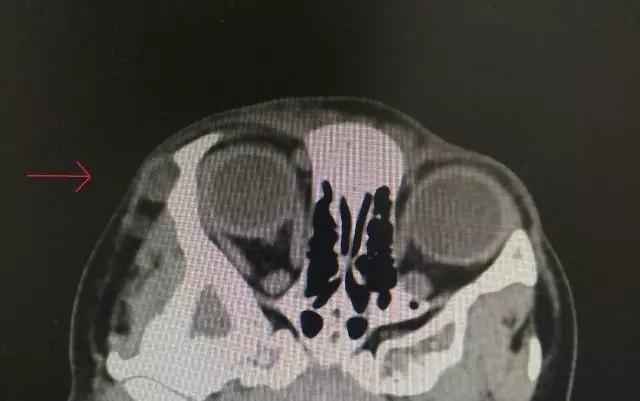

虽然表皮样囊肿相对表浅,但有的可以长得很深很大,甚至深达眼眶内,造成取出困难,甚至会损伤周边重要的组织

肿物常常边界清晰,如花生豆样,如果未能完整取出,残留囊膜有复发之可能